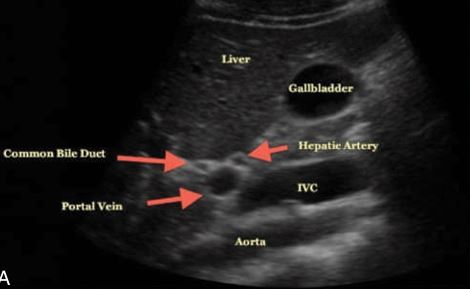

1. Portal Vein

2. Common Bile Duct

3. Gallbladder

arrow: MLF

curved arrow: portal vein

arrow: CBD

curved arrow: CBD

arrow: HA

Common Bile Duct doesn’t catch COLOR

On this sagittal image, the hepatic artery (HA) is shown anterior to the common duct (CD)